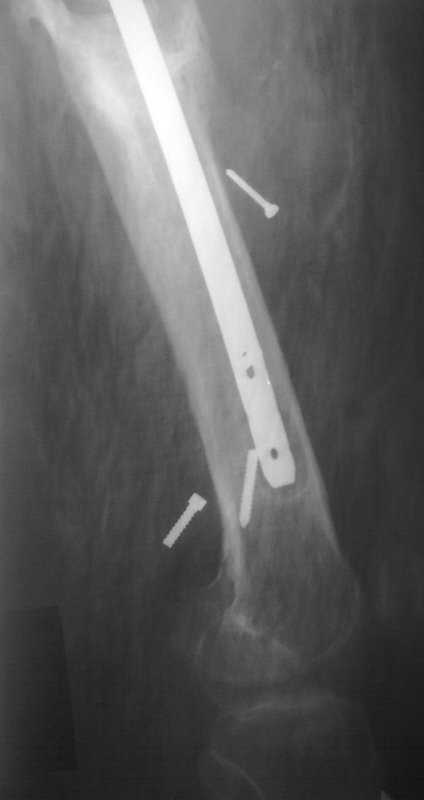

[Ortho] Псевдоартроз бедренной кости, инфекция.

Здравствуйте уважаемые коллеги, прошу Вашего мнения относительно тактики лечения пациента М. 37 лет, рост 170 см. вес 140 кг.

Анамнез: пострадал в рез. ДТП в 2004 году, лечился в одной из районных больниц гдебыл прооперирован DCP.

в 2006 году перелом м/фиксатора с последующим реостеосинтезом стержнем Кюнчера без блокирования.

в 2007 году перелом фиксатора после чего обратился в нашу клинику, где было произведено удаление гвоздя, БИОС L-360 mm D-12 mm с кортико-спонгиозной пластикой, в теч. 6-и мес. больной был под наблюдением динамизация ч-з 2 мес. после чего пациент исчез с поля зрения.

Появился с жалобами на болезненность в месте перелома, укорочение ноги, в течении года поочередно в ягодичной области и н/3 бедра функционирующие свищи.

На данный момент имеем свищ в н\3 бедра, укорочение ноги на 3 см, внешняя ротация.Произведена фистулография, взят посев из свищевого хода.